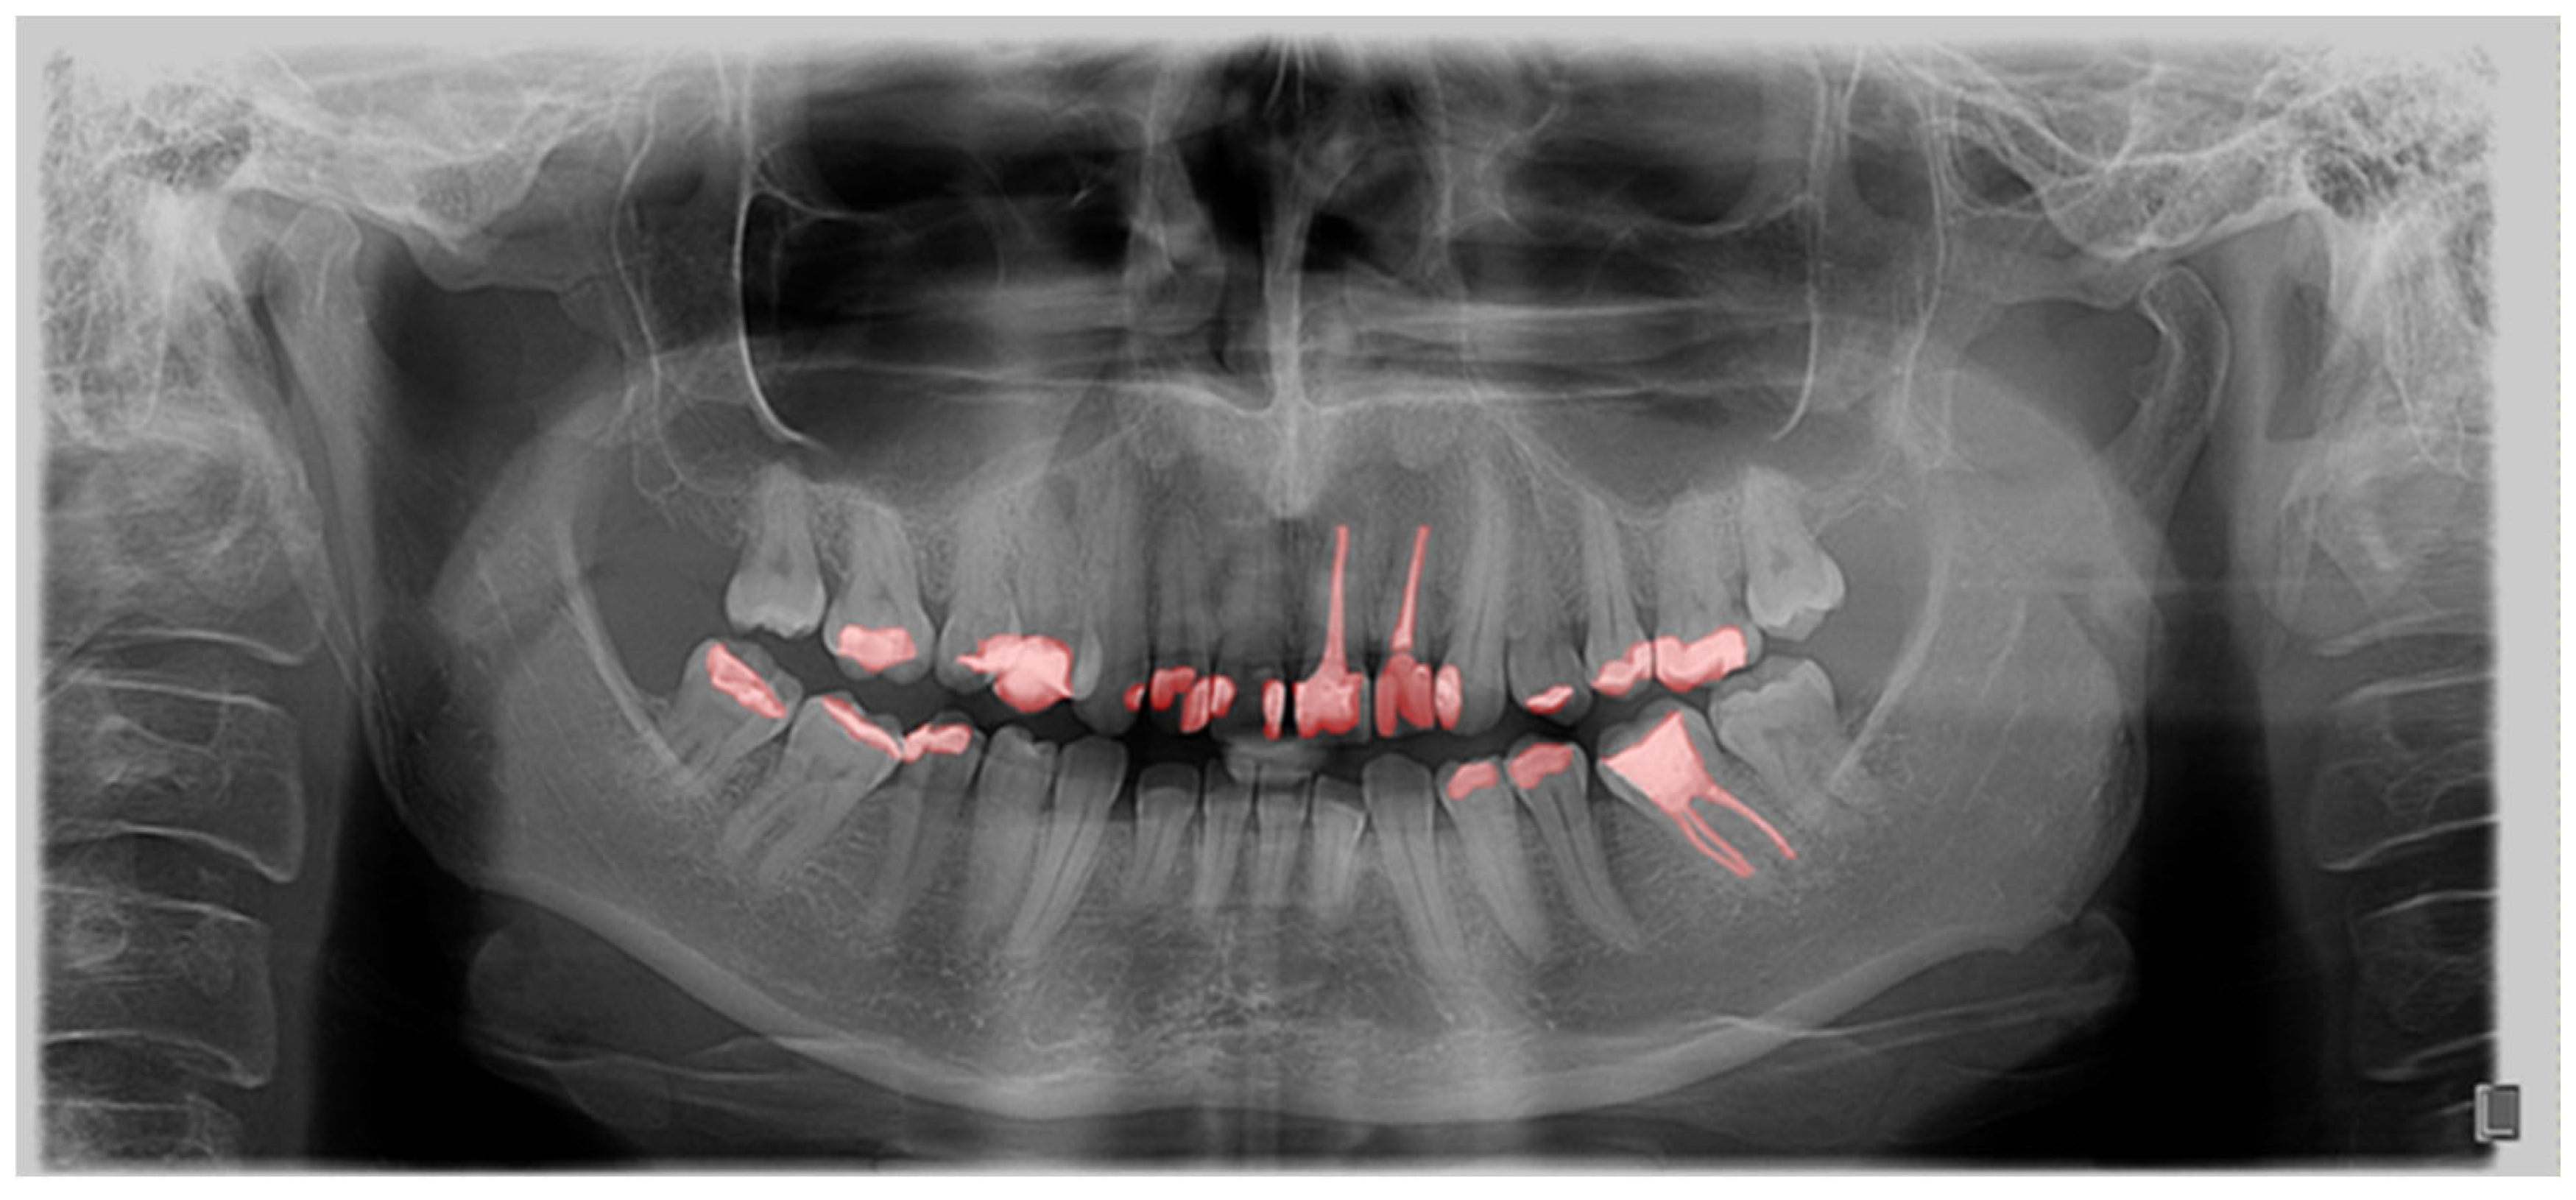

Furthermore, the findings were assessed across the complete OPGs, as well as in relation to segmented teeth (teeth separated from adjacent structures) and individual teeth. These individual teeth were marked in bounding boxes where the most prominent pixels were used as box margins (Figure 3).

Figure 3. Bounding box generated based on the segmented tooth marginal pixels.